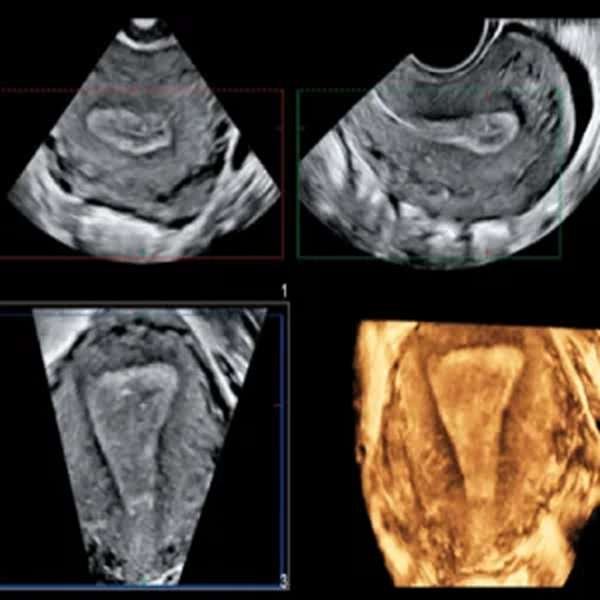

Ecografía Morfológica 3D | 4D

La ecografía morfológica 3D/4D es un estudio avanzado que combina el análisis detallado de la anatomía fetal con imágenes tridimensionales en tiempo real. Se realiza entre las semanas 18 y 24 del embarazo para evaluar el desarrollo de órganos, extremidades y el sistema nervioso, permitiendo detectar posibles malformaciones congénitas. La tecnología 3D ofrece imágenes estáticas de alta resolución, mientras que la 4D muestra los movimientos del bebé en tiempo real. Es un procedimiento seguro e indoloro que proporciona un diagnóstico preciso y una experiencia más emocional para los padres.